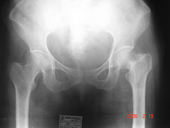

| Fracture neck of femur pre op |

Fracture neck of femur post op |